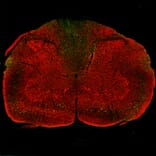

A Keyence merged image of an entire coronal section from a of rat given a contusion injury three days previously and stained for Anti-NF-L Antibody (red) and Anti-NF L Antibody [1D44] (A333277) (green). Anti-NF L Antibody [1D44] (A333277) positive profiles are particularly obvious in the dorsal columns, corticospinal tracts and rubrospinal tracts, less abundant in the lateral and ventral funuculi and least abundant but not totally absent in the spinal cord gray matter.